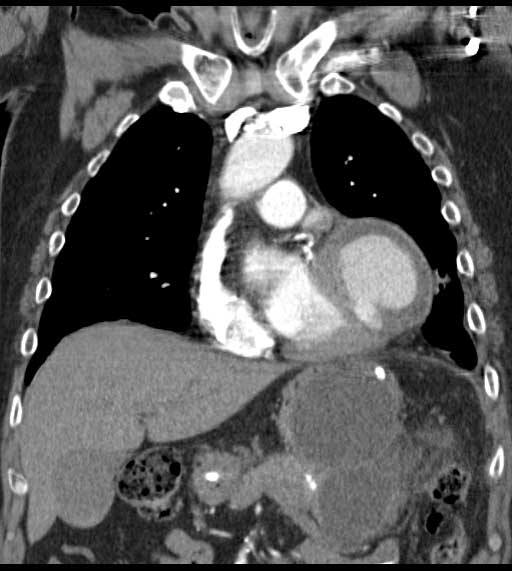

| Figure 1 & 2. Preoperative CT-scan | |

We report a case of a 78 y/o male with history of CAD, for which he underwent coronary artery by-pass surgery in 2004. The patient was admitted to the hospital with symptoms of moderate congestive heart failure. EKG showed no signs of acute ischemia and cardiac enzymes were negative. Cardiac ECHO showed a 6.8 x 5 cm pseudoaneurysm of the posterior left ventricle, well preserved ventricular function and no abnormalities of the mitral and aortic valves. Coronary angiogram demonstrated patency of all previous bypasses. The chest CT allowed better definition of the anatomy of the condition (Figure 1, 2). The procedure was performed through an antero-lateral left thoracotomy positioning the patient in a right lateral decubitus. The chest was entered at the 5th intercostal space and the sterno-costal junction was interrupted to optimize exposure. The left lung was displaced posteriorly and the pericardium was opened longitudinally and posteriorly to the phrenic nerve. Dissection of the heart surface from the pericardium was easily completed obtaining perfect exposure of the left ventricular pseudo-aneurysm. The previous by-pass grafts were never visualized, being distant from the operative field. Cardiopulmonary bypass was established through the left femoral vessels using a 17 F arterial femoral cannula and a 25 F multistage venous femoral cannula. The left ventricle was vented through the apex using a 10 F suction catheter. Systemic pressure was kept above 70 mmHg and the heart was decompressed before entering the left ventricular cavity via a longitudinal incision through the wall of the pseudoaneurysm (Figure 3). A bovine patch pericardial repair was completed with interrupted pledgetted sutures maintaining the architecture of the left ventricle (Figure 4). The closure was reinforced overlapping the wall of the pseudoaneurysm over the patch closure (Figure 5). Meticulous de-airing was completed under TTE monitoring before allowing ejection of the left ventricle into the circulation. De-airing was accomplished placing the patient in steep Trendelemburg position and maintaining full suction on the apical vent. Cardioplulmonary bypass was weaned-off without complications. The patient postoperative course was uncomplicated and he was discharged home in postoperative day 6. The postoperative CT-scan image is shown (Figure 6).